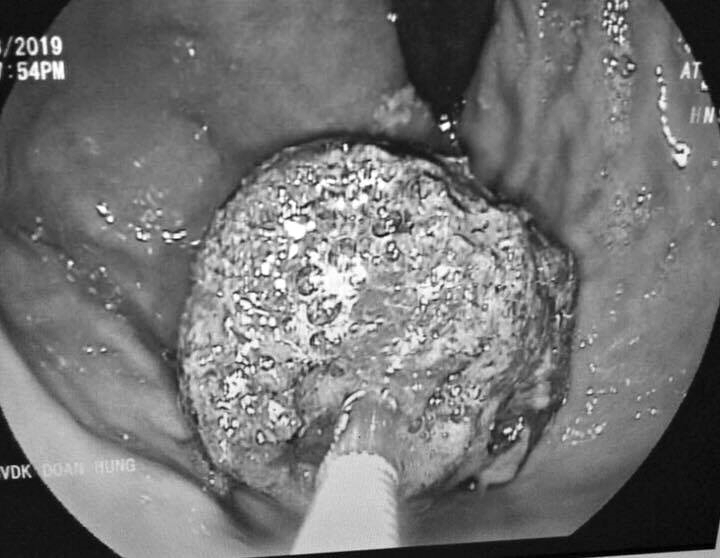

Mới đây 1 thanh niên ở Phú Thọ đã phải nhập viện trong tình trạng bụng đau dữ dội trong nhiều ngày. Sau khi kiểm tra các bác sĩ cho biết có 1 khối thức ăn bị tắc bên trong cần phải lấy ra. Được biết thanh niên này thường xuyên uống trà sữa trong thời gian dài.Bệnh viện Đa khoa tỉnh Phú Thọ cho biết, ngày 19/8 vừa qua, bệnh viện tiếp nhận trường hợp nam thanh niên N.L., 20 tuổi, trú tại Hạ Hòa, tỉnh Phú Thọ trong tình trạng đau bụng nhiều, nôn, bụng chướng.

gia đình cho biết, anh L. có thói quen ăn uống không khoa học, thường xuyên uống trà sữa bỏ cơm. Trước khi vào viện khoảng 6 ngày, anh L. có biểu hiện đau bụng dữ dội, được người nhà đưa vào bệnh viện tuyến huyện.

Tuy nhiên, sau khoảng 5 ngày điều trị, tình trạng bệnh không thuyên giảm, anh L. tiếp tục được chuyển lên Bệnh viện Đa khoa tỉnh Phú Thọ.Tại đây, kết quả chụp cắt lớp cho thấy, bệnh nhân bị tắc ruột do bã, quai ruột giãn to. Để điều trị, người bệnh được chỉ định phẫu thuật mở ruột, mở dạ dày lấy bã thức ăn.

Quá trình mổ các bác sĩ đã lấy ra 2 khối bã thức ăn lớn trong dạ dày và ruột non bệnh nhân. Hiện tại, tình trạng bệnh nhân dần ổn định và đang tiếp tục theo dõi sức khỏe tại bệnh viện.

Theo BS Trần Thanh Tùng - Bệnh viện Đa khoa tỉnh Phú Thọ, trường hợp của bệnh nhân L. nếu không được phát hiện sớm và điều trị kịp thời thì nguy cơ nhiễm trùng, nhiễm độc cao, hoại tử ruột, suy đa tạng, thậm chí ảnh hưởng đến tính mạng.

Bác sĩ Tùng khuyến cáo, để tránh lâm tình trạng trên, người dân cần tuân thủ tuyệt đối ăn chín, uống sôi, hạn chế ăn đồ ăn nhanh, ăn vặt, tránh uống quá nhiều nước ngọt, nước có ga hay trà sữa trong thời gian dài... Ngoài ra, người dân cũng cần tẩy giun theo định kỳ.